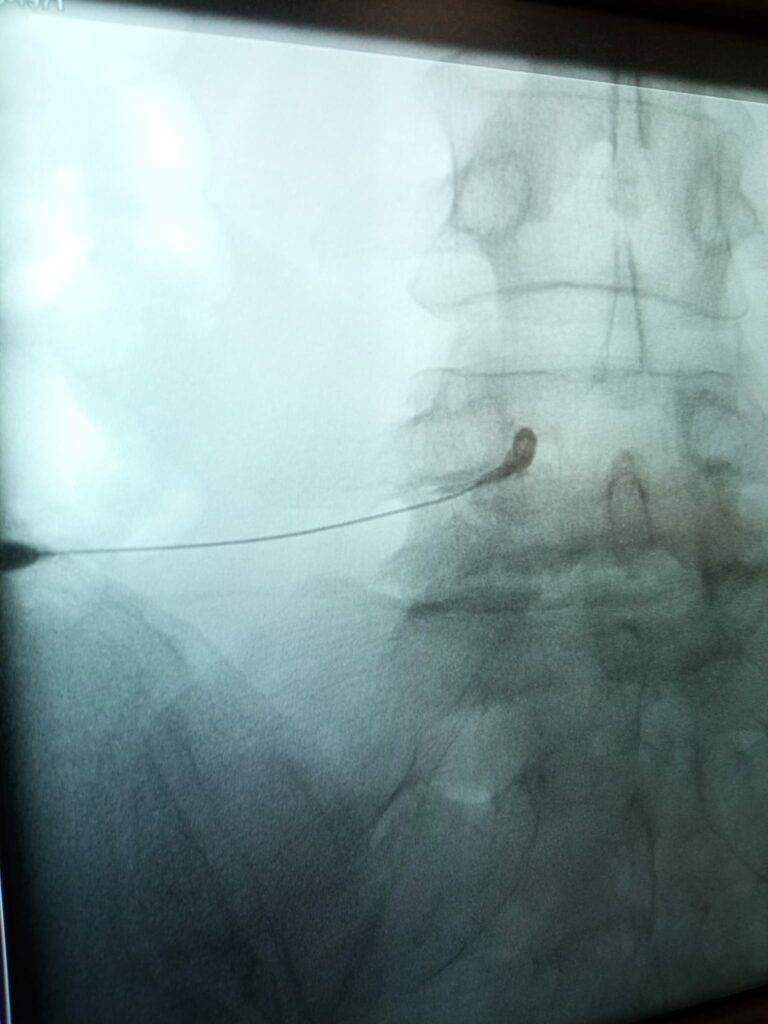

Ryc. 1. Radiogram wykonany podczas przezotworowej iniekcji dokonałowej z zastosowaniem kontrastu (koniec igły) potwierdzającego prawidłową dystrybucję leku.